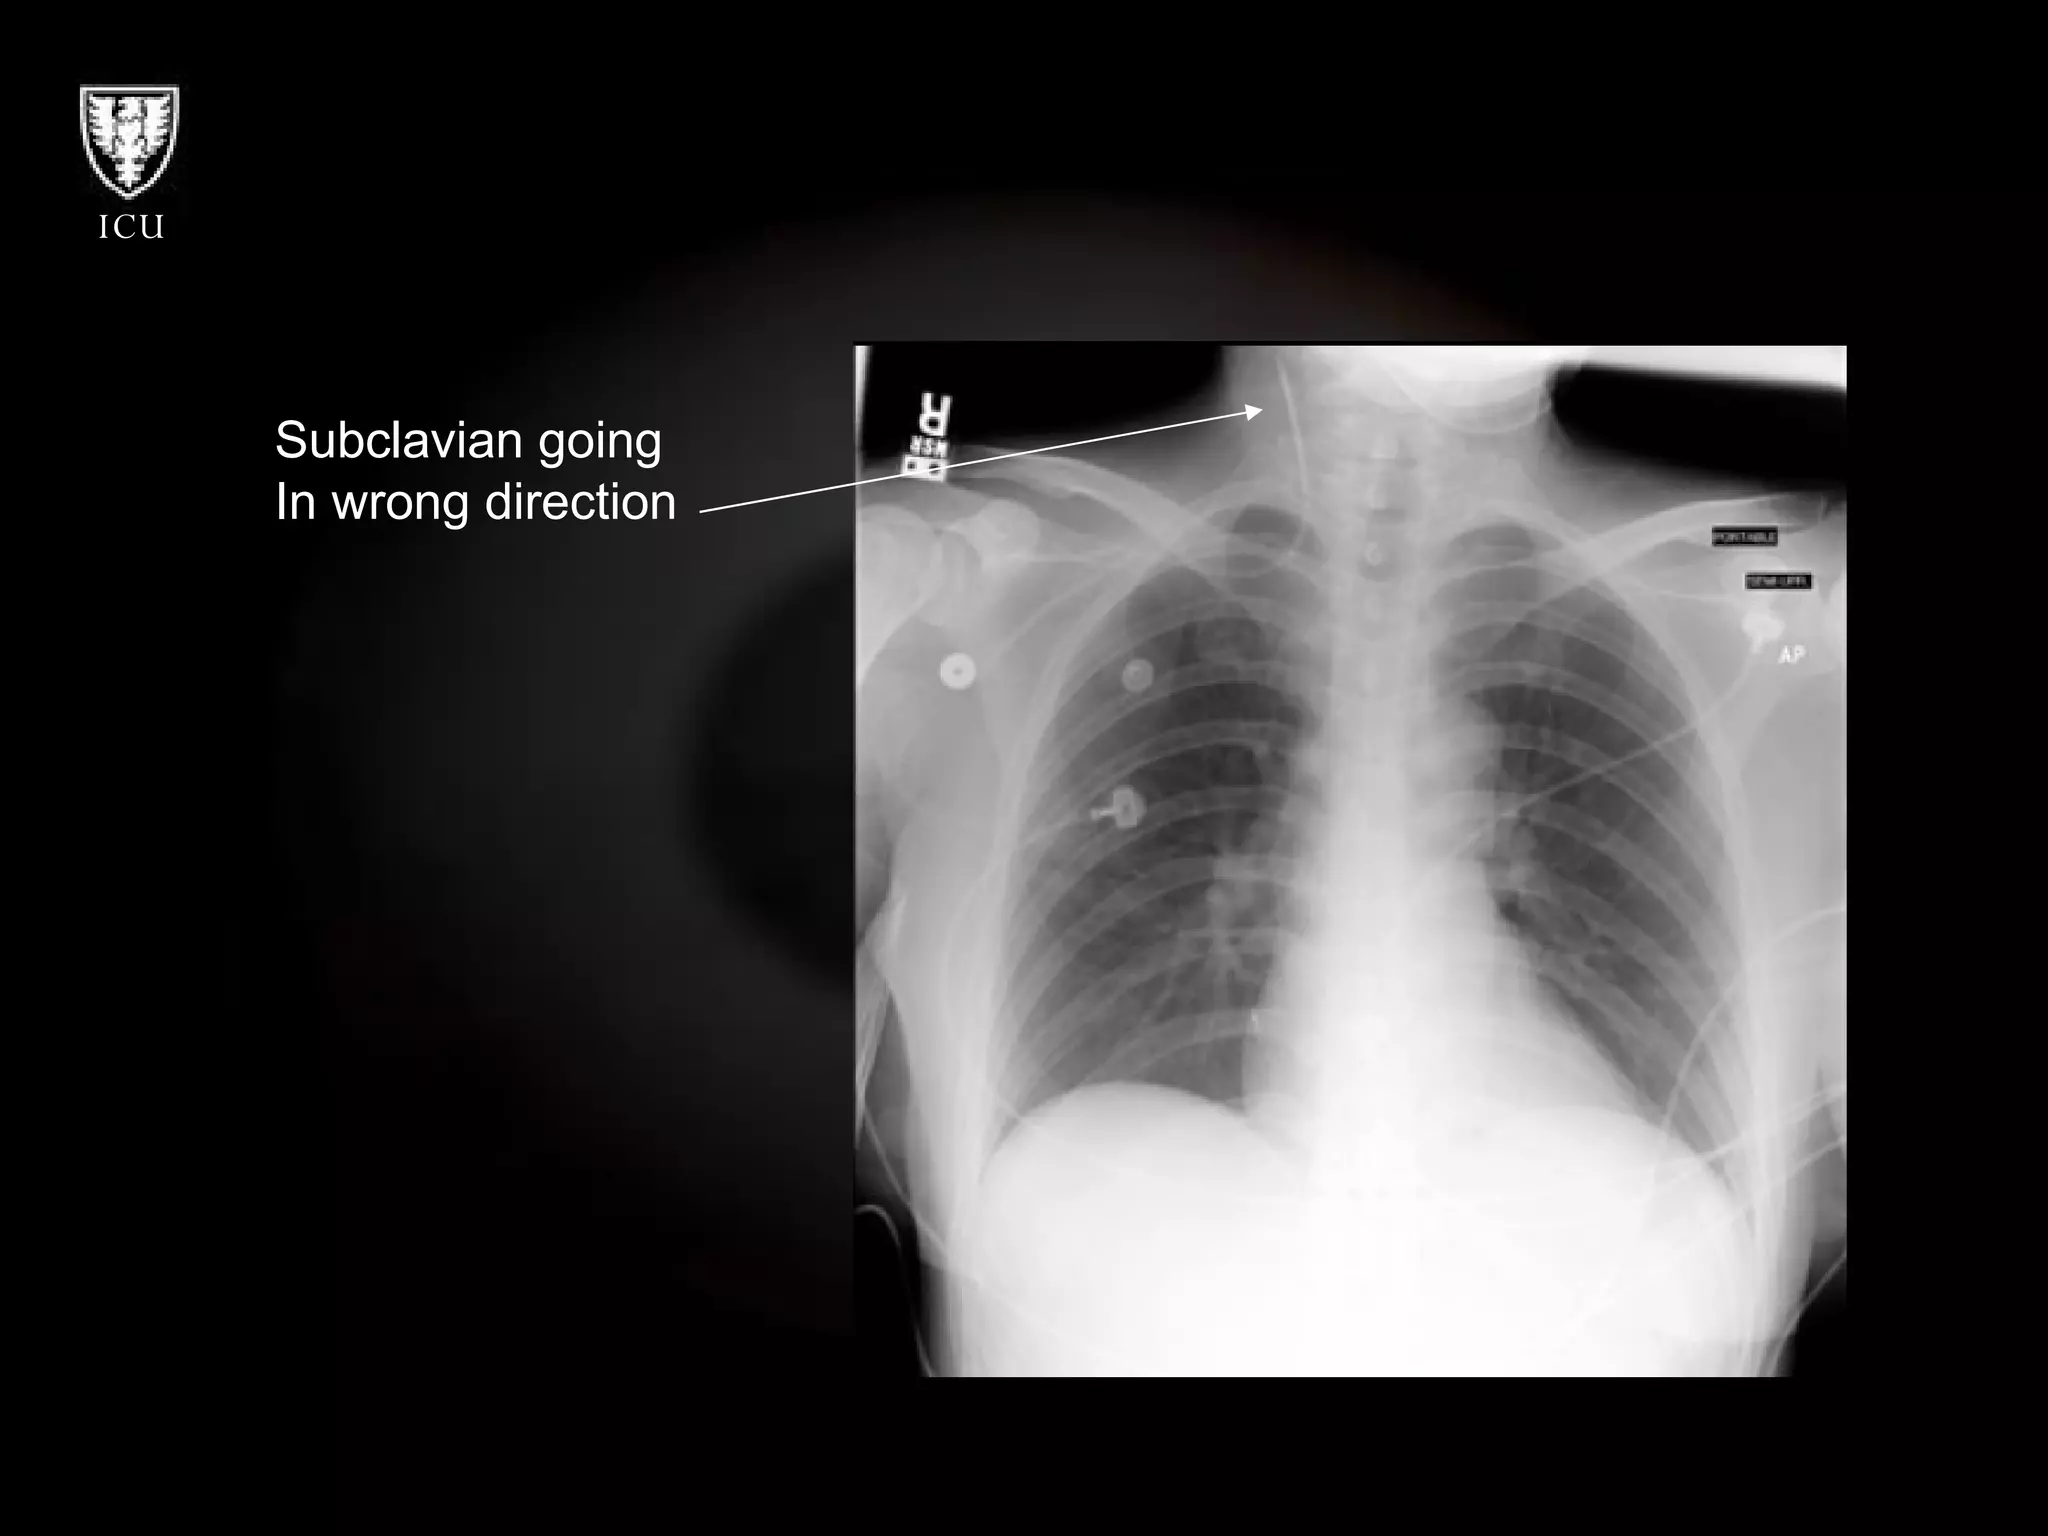

What’s Wrong With These Pictures?

Subclavian going  In wrong direction

What’s Wrong WithThese Pictures?